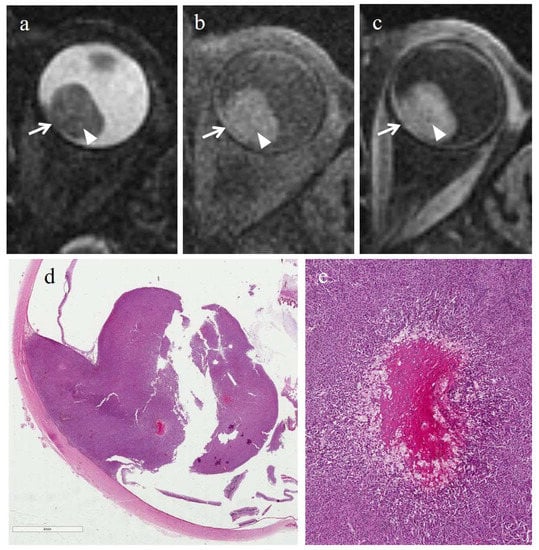

3.2.2. Histopathologic Findings in the Control Group

3.3.2. MRI Findings in the Control Group

| Patient | Histologic Type | Degree of Pigmentation | Degree of Necrosis | Necrotic Pattern |

|---|---|---|---|---|

| 1 | Epithelioid cell | Pigmented | Grade I | Multiple foci- hemorrhagic/coagulative-type, tumor necrosis |

| 2 | Epithelioid cell | Poorly pigmented | Grade I | Multiple foci- hemorrhagic/coagulative-type, tumor necrosis |

| 3 | Spindle cell | Pigmented | Grade II | Multiple foci tumor necrosis |

| 4 | Mixed cell type | Pigmented | Grade I | Multiple foci tumor necrosis |

| 5 | Spindle cell | Pigmented | Grade I | Multiple foci- hemorrhagic/coagulative-type, tumor necrosis |

| 6 | Mixed cell type | Poorly pigmented | Grade I | Multiple foci- hemorrhagic/coagulative-type |

| Patient | T2 | T1 | Gd-T1 | DWI | ADC × 10−3 mm2/s ** |

|---|---|---|---|---|---|

| 1 | - | - | - | - | 1.04 |

| 2 | - | - | - | - | 1.22 |

| 3 | - | - | - | - | 0.63 |

| 4 | - | - | - | - | 0.78 |

| 5 | - | - | - | - | 1.05 |

| 6 | Hyperintense | Hypointense | No enhancement | No restriction | 0.80 |